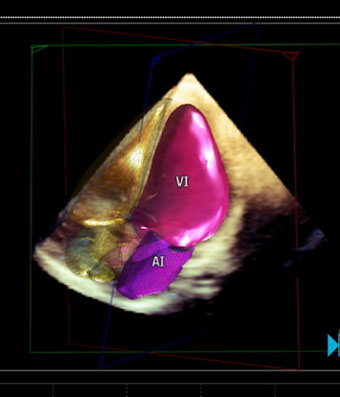

El ecocardiograma o ecocardiografía utiliza ondas sonoras de alta frecuencia para obtener imágenes del corazón en vivo y que son proyectadas en una pantalla. Este auxiliar diagnóstico aporta información en 30 a 60 minutos de la forma, tamaño, función y movimiento del corazón así como de sus estructuras internas, como por ejemplo las válvulas cardiacas. Este estudio es seguro en pacientes adultos, en pacientes pediátricos (ecocardiograma pediátrico) o incluso en mujeres embazadas para estudiar el desarrollo del corazón del bebé en la cavidad uterina (ecocardiografía fetal).

Las imágenes ecocardiografías del corazón pueden ser obtenidas en diferentes modos (unidimensional, bidimensional o tridimensional, Doppler, Doppler color), utilizando una sonda externa (ecocardiograma transtorácico) o una sonda interna (ecocardiograma transesofágico) y puede ser adquirido en reposo, en estrés con esfuerzo físico o con el uso de medicamentos (estrés con dobutamina), dependiendo del diagnóstico y de la indicación de tú médico.